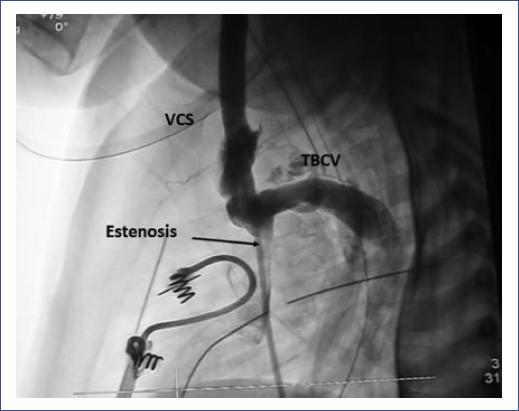

Mediante un cateterismo diagnóstico e intervencionista, se confirmó la obstrucción severa de la VCS mediante venografía (Fig. 2). Posteriormente, se realizó angioplastia secuencial en la VCS con catéter balón SterlingMR 6 x 20 mm, 8 x 20 mm hasta 14 atm en tres ocasiones. El procedimiento se repitió con balón MustangMR 12 x 20 mm, obteniendo un gradiente inicial de 27 mmHg y final de 15 mmHg, por lo que se decidió colocar stent Palmaz Génesis Trashepatic billar StentMR 10 x 17 mm, el cual se entregó en sitio de estenosis sin complicaciones y con gradiente final de 0 mmHg (Fig. 3).

Figura 2 Angiografía en la vena cava superior. Se visualiza obstrucción parcial (flecha) en la región comprendida entre el tronco braquiocefálico venoso y la desembocadura al atrio derecho. VCS: vena cava superior; TBCV: tronco braquiocefálico venoso.